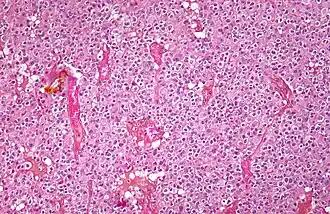

Micrograph of an oligodendroglioma showing the characteristic branching, small, chicken wire-like blood vessels and fried egg-like cells, with clear cytoplasm and well-defined cell borders. H&E stain.

Oligodendrogliomas cannot currently be differentiated from other brain lesions solely by their clinical or radiographic appearance. As such, a brain biopsy is the only method of definitive diagnosis. Oligodendrogliomas recapitulate the appearance of the normal resident oligodendroglia of the brain. (Their name derives from the Greek roots 'oligo' meaning "few" and 'dendro' meaning "trees".) They are generally composed of cells with small to slightly enlarged round nuclei with dark, compact nuclei and a small amount of eosinophilic cytoplasm. They are often referred to as "fried egg" cells due to their histologic appearance (though, the perinuclear halo on permanent sections is an artifact of tissue drying; fresh tissue lacks this characteristic "fried egg" appearance). They appear as a monotonous population of mildly enlarged round cells infiltrating normal brain parenchyma and producing vague nodules. Although the tumor may appear to be vaguely circumscribed, it is by definition a diffusely infiltrating tumor.[6]

Classically they tend to have a vasculature of finely branching capillaries that may take on a "chicken wire" appearance. When invading grey matter structures such as cortex, the neoplastic oligodendrocytes tend to cluster around neurons exhibiting a phenomenon referred to as "perineuronal satellitosis". Oligodendrogliomas may invade preferentially around vessels or under the pial surface of the brain.[6]